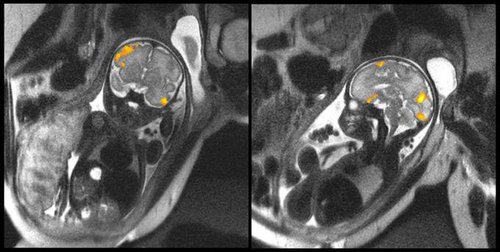

Na powyższym zdjęciu możemy zobaczyć wyniki rezonansu magnetycznego płodu w 20 oraz w 40 tygodniu życia. Obrazy uzyskano w Uniwersytecie Stanowym Wayne w Michigan w Stanach Zjednoczonych. Zdjęcia te umożliwiają ocenę aktywności mózgowej płodu w łonie matki.

Najważniejszym celem naukowców uzyskujących takie obrazy jest badanie jakości połączeń nerwowych nienarodzonego jeszcze dziecka w ostatnich tygodniach przed rozwiązaniem. Badania te umożliwiają zrozumienie jak dotąd nieznanych aspektów związanych z rozwojem płodu.